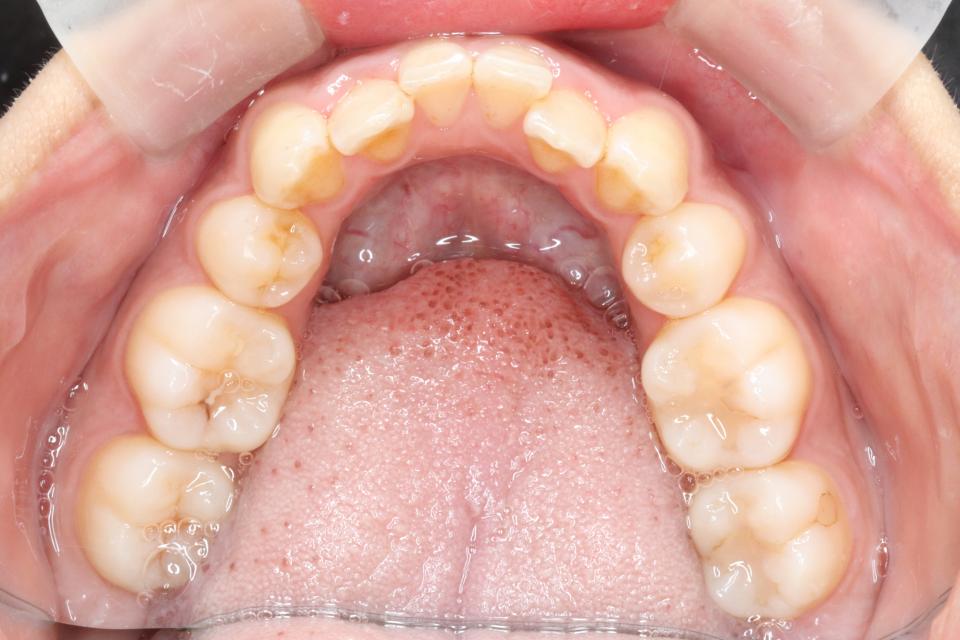

矯正治療後

マウスピース型の矯正治療装置を使用し、前歯の歯並びのみの改善を行いました。

現在は保定装置を使用し定期的にチェックしています。